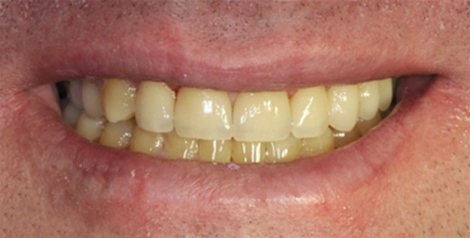

ДО

Пациент обратился с жалобой на истирание передней и боковой групп зубов, отсутствие жевательных зубов, затрудненное пережевывание пищи, ухудшение дикции, появление морщин в уголках рта.